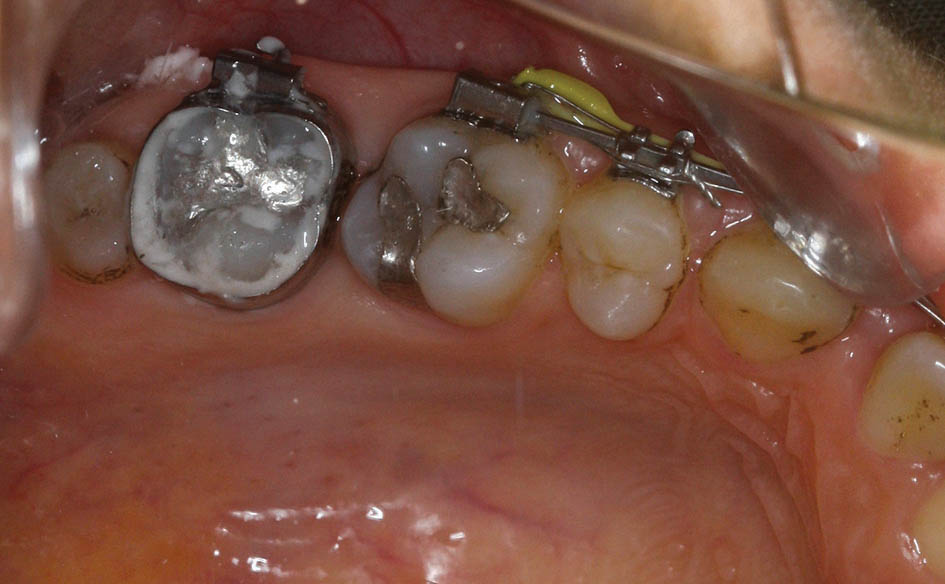

در زمان بستن فضا محل اعمال نیرو روی ناحیه خلفی، باکال تیوب مولر اول است، لذا باکال آن بیشتر مزیاله و سمت لینگوال کمتر مزیاله میشود. این بدان معنی است که در حین بستن فضا مولر اول دچار چرخش میشود، لذا بعد از مدتی دیگر فضا بسته نمیشود (شکل 23-3). در موارد کشیدنی برای جلوگیری از این حالت حتماً باید دندان هفت را بچسبانید تا انتهای سیم درون تیوب هفت باشد.

شکل 23-3: نیروی بستن فضا روی مولر اول باعث چرخش آن شده است. چسباندن براکت مولر دوم و قرار دادن سیم درون آن مانع چرخش مولر اول در زمان بستن فضا میشود.

انتهای سیم انعطاف پذیری بالایی دارد، لذا اگر تا مولر اول چسبانده باشید و Active Tieback را به آن بزنید بخاطر انعطاف بالای سیم، مولر اول سریع دچار چرخش میشود. اگر تا مولر دوم بچسبانید و سیم درون باکال تیوب مولر دوم باشد در این صورت وسط سیم درون باکال تیوب مولر اول قرار خواهد داشت که انعطاف کمتری دارد، لذا کمتر دچار چرخش میشود. چرخش مولر اول یک مانع اصلی در زمان بسته شدن فضا است و بدین صورت با قراردادن انتهای سیم درون مولر دوم باعث بسته شدن راحت فضا میشویم.